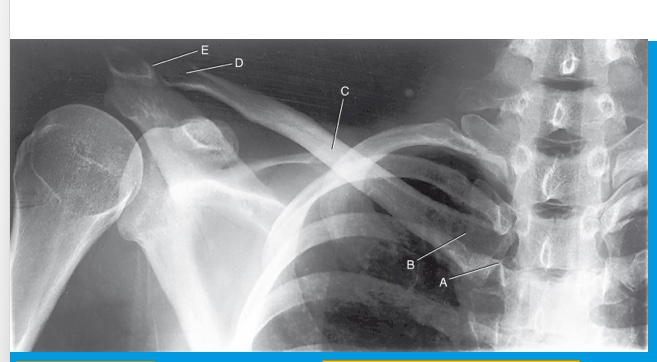

SC joint

A

sternal extremity

B

body

C

acromial extremity

D

AC joint

E